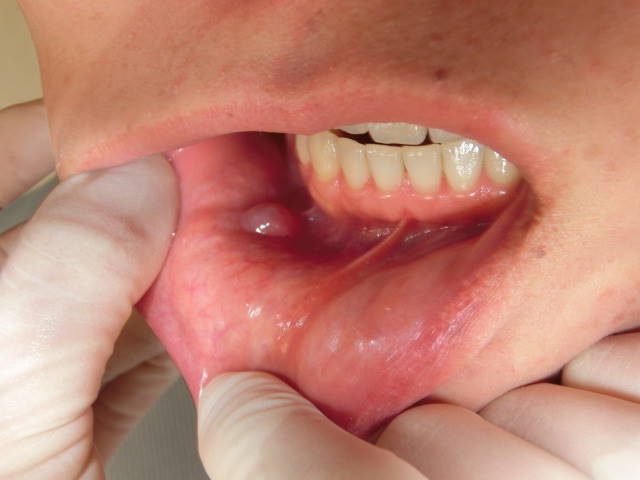

症例1:下唇粘液嚢胞

11歳 女性。

数ヶ月前より腫脹を自覚していましたが、消退・腫脹を繰り返すため受診。

局所麻酔下に、直下の小唾液腺を含めて摘出しました。

一般的に、粘液嚢胞の手術時間は15分程度です。